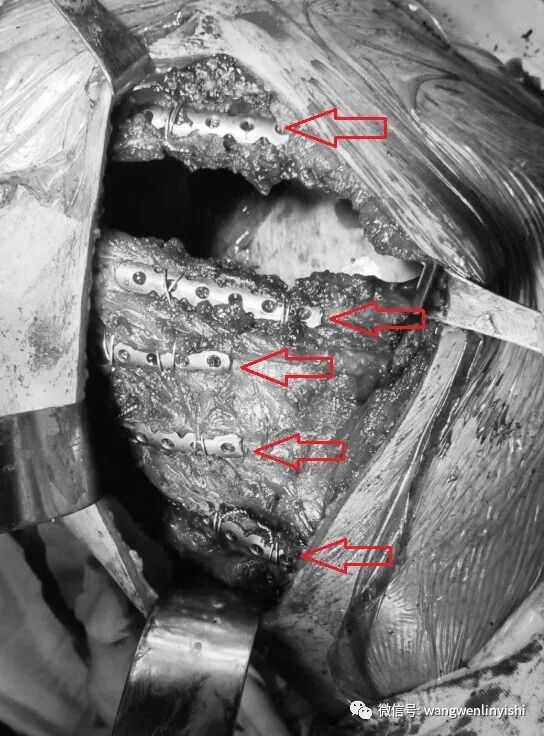

(以MatrixRIB对右侧第6、7、8、9、10肋骨骨折进行固定,均采用钢丝直接固定)

(以MatrixRIB对右侧第9、10肋骨后肋粉碎性骨折畸形固定,均采用钢丝固定,共三处,六条钢丝)

在对肋骨骨折固定的过程中,我们全部采用钢丝做固定。这种方法的优点是:(1)操作方便。以带针的钢丝环绕钢丝与MatrixRIB做固定,操作非常简单,且不需要特殊装置;(2)固定效果确切。我们采用双钢丝环绕固定,钢板每一端只需要固定一次,可以获得非常满意的效果;(3)对一些特殊骨折类型有好的效果。钢丝固定可以满足所有特殊情况的固定,比如存在骨质疏松、骨骼裂开的情况时,由于使用螺丝钉固定效果不佳,此时采用钢丝固定将有很好的效果;(4)当骨折部位显露困难时,可有好的效果。经过特定切口实施肋骨骨折固定时,有些部位的骨折显露困难,如果用螺丝钉固定,难度很大。此时如果用钢丝做固定,操作极其方便,可以轻易完成手术。

我们具体的操作是,先于脊柱旁的肋骨残端处置放钢丝,将MatrixRIB与肋骨残端固定;再于肋骨断段的前部残端放置钢丝,将其与MatrixRIB的另一端牢固固定。两端固定完毕后,于中间完全游离的肋骨处放置钢丝,将此游离的肋骨段与MatrixRIB中部牢固固定。经过三处固定后,粉碎性骨折可以轻易得到固定,而且可以获得近乎完美的复位效果。

粉碎性肋骨骨折使用MatrixRIB进行矫正时,如果采用经典的螺丝钉做固定,中间粉碎的部位很难固定满意,两端的肋骨主干如果有裂隙,同样会影响螺丝钉固定的稳定性,因此这种骨折对固定方法是一种大的挑战。采用钢丝固定不仅可以使不可能变为可能,而且具有明确的优点。除了上述的几种优点外,由于采取三道钢丝固定,而每一道都是双钢丝,这相当于用六条钢丝完成的固定操作,因此不仅效果确切,而且可以保证骨折处完全复位,获得最完美的固定效果。